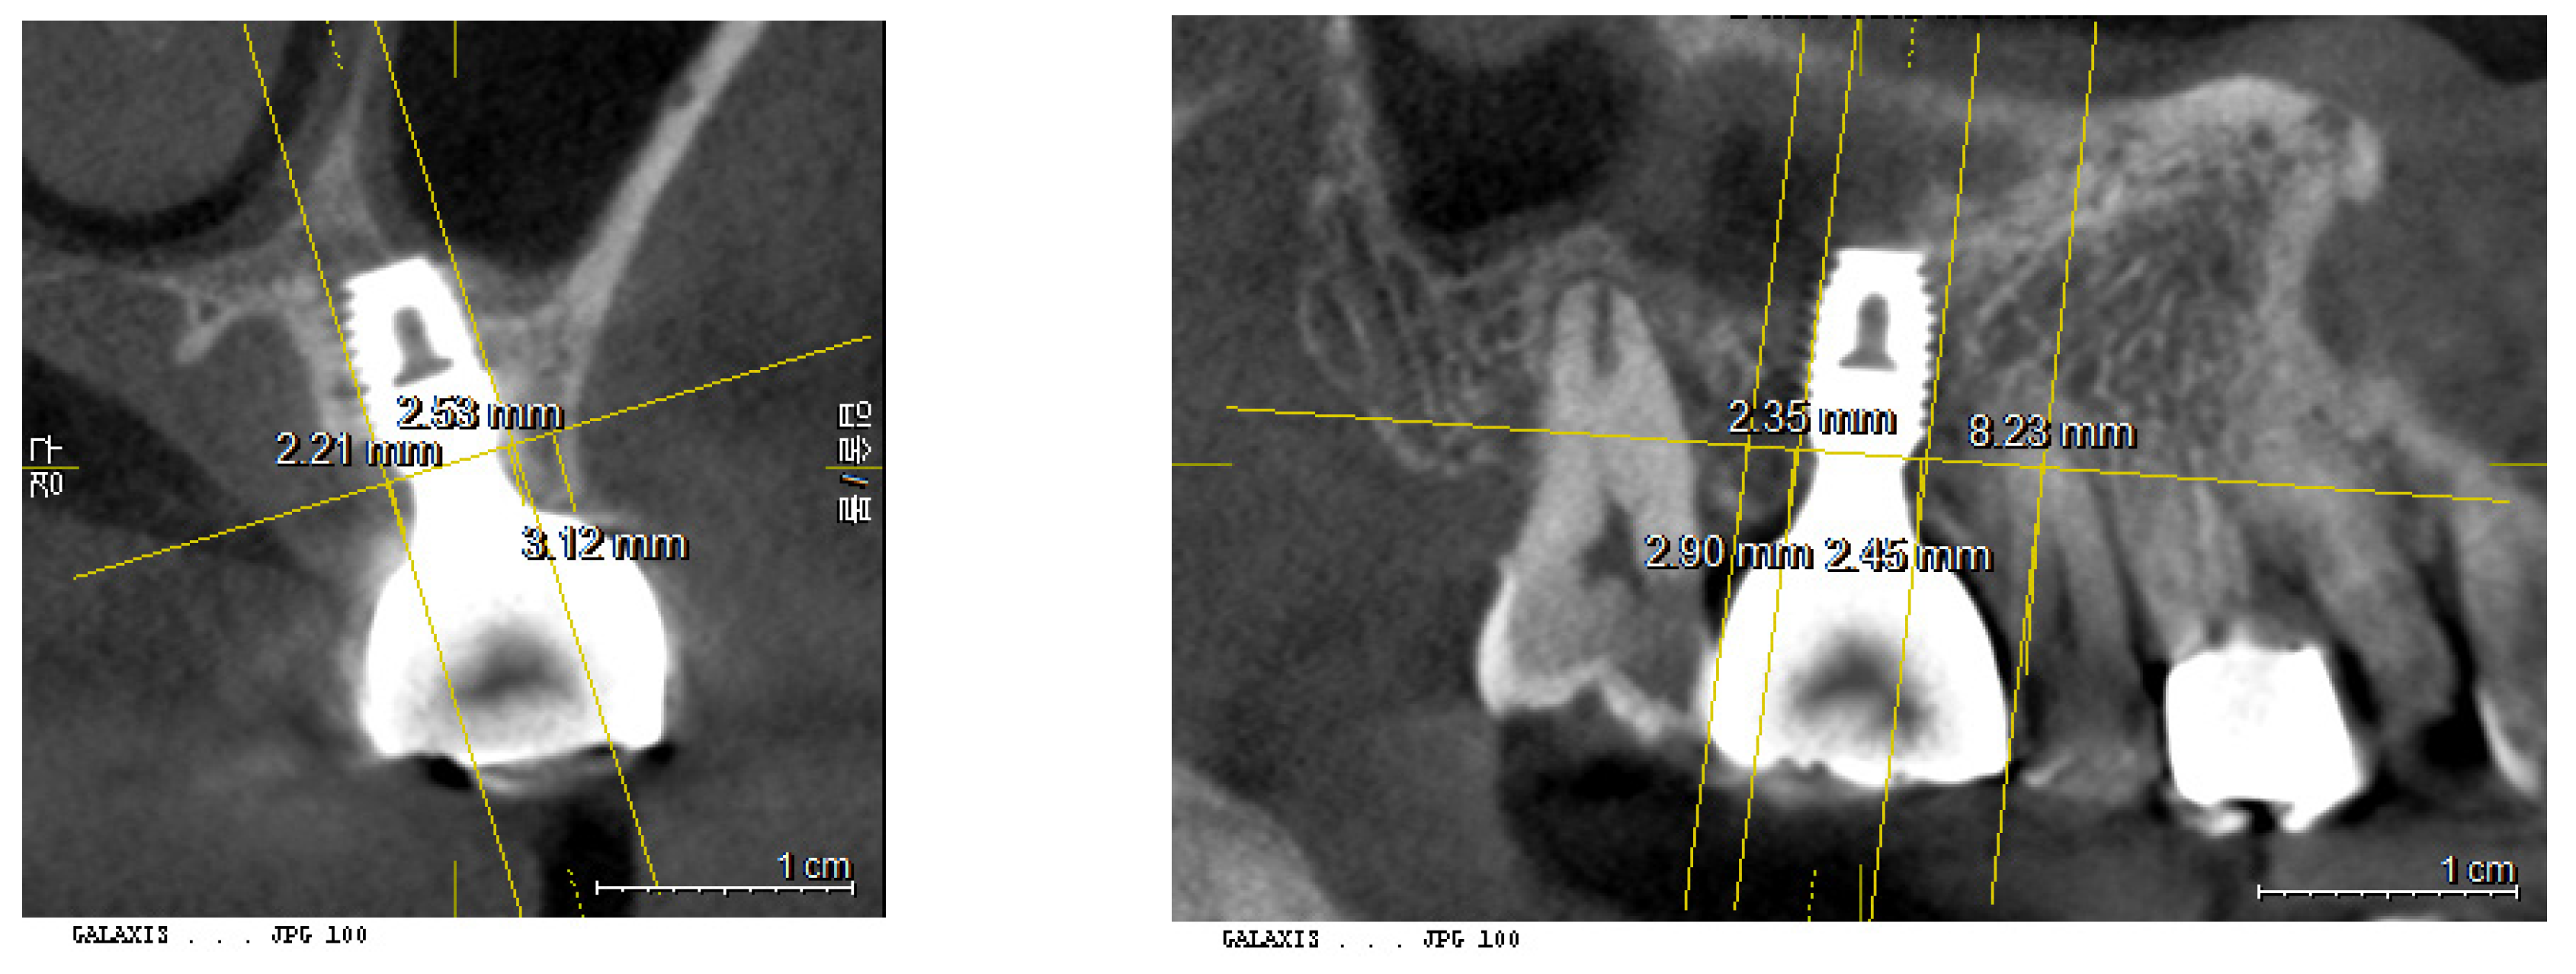

4. Crestal Bone Thickness (CBT) from CBCT - 3DSTA

Crestal Bone Thickness is measured buccolingually, focusing solely on the dimension from the most inner point of the crestal bone contacting the fixture at the level of the fixture top, to the most outer point of the surrounding crestal bone. This specific measurement provides critical information regarding the thickness and health of the bone encompassing the implant, which is vital for assessing the stability and long-term viability of the implant.

5. Crestal Bone Length (CBL) = Transitional Zone Length from CBCT - 3DSTA

Crestal Bone Length, corresponding to the Transitional Zone Length, is measured as long as the peripheral soft tissue thickness between the crown-abutment complex and the surface of the crestal bone is maintained within 1.0 mm. The measurement is taken from the most inner contacting point of crestal bone with the fixture to the most outer point of crestal bone, conducted both buccolingually and mesiodistally. It can be regarded as the horizontal component of the soft tissue surrounding the implants.

Enhanced Biologic Sealing in SPIs: A CBCT Analysis of Transmucosal Soft Tissue Dimensions

The cases examined in this study demonstrate that the area of transmucosal soft tissue, which corresponds to the junctional epithelium and connective tissue (the biologic width), around dental implants is enlarged due to deep subcrestal placement. This enlargement was quantitatively analyzed using Cone Beam Computed Tomography (CBCT). The results indicated that the average length of the Transitional Zone (TZ) was 3.8 mm, with an average thickness of 0.6 mm. These measurements suggest that the majority of the TZ is composed primarily of connective tissue. As the TZ extends toward the peripheral area and its thickness increases to more than 1.0-1.5 mm, it typically becomes covered with junctional epithelium. The predominant structure of the submucosal area is a connective tissue zone with junctional epithelium primarily present at the entrance, measuring approximately 0.5-1 mm, as detailed by Ikiru Atsuta et al.^[30].